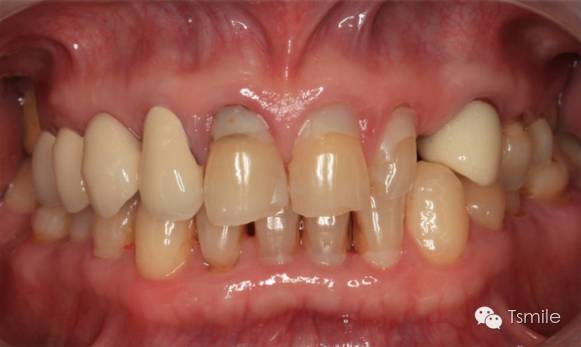

牙列重度磨耗的患者,特別是全牙列重度磨耗的患者,其口腔美觀和功能都受到了嚴(yán)重影響。患者不僅需要口腔美學(xué)重建,還需要口腔功能的重建。

例如面對(duì)一個(gè)牙列重度磨耗的美學(xué)修復(fù)患者,我們首先根據(jù)患者主訴和美學(xué)檢查形成美學(xué)設(shè)計(jì),然后通過數(shù)碼圖像表達(dá)美學(xué)設(shè)計(jì)思想,制作診斷蠟型,口內(nèi)制作診斷飾面,更加真實(shí)地表達(dá)美學(xué)設(shè)計(jì)。根據(jù)患者的要求和口內(nèi)試戴情況調(diào)改診斷飾面,最終確定美學(xué)修復(fù)設(shè)計(jì),即最終修復(fù)體的各種美學(xué)參數(shù)。接下來就是美學(xué)實(shí)現(xiàn)過程,在診斷飾面上進(jìn)行精確地牙體預(yù)備,制取印模和工作模型,技師按照最終診斷飾面的形態(tài)、大小和排列制作最終美學(xué)修復(fù)體,最后完成修復(fù)體粘接。

在前牙的美學(xué)分析中有四個(gè)最重要的美學(xué)影響因素,稱之為前牙美學(xué)四要素。包括上中切牙切緣的位置、上中切牙臨床冠的寬長(zhǎng)比、上中切牙齦緣的位置、上前牙的寬度比例。這四要素是影響前牙美學(xué)的主要因素,根據(jù)這四要素就可以簡(jiǎn)單、快速、準(zhǔn)確地分析患者前牙存在的美學(xué)缺陷。根據(jù)這四因素就可以準(zhǔn)確、直接地進(jìn)行患者前牙的美學(xué)修復(fù)設(shè)計(jì)。